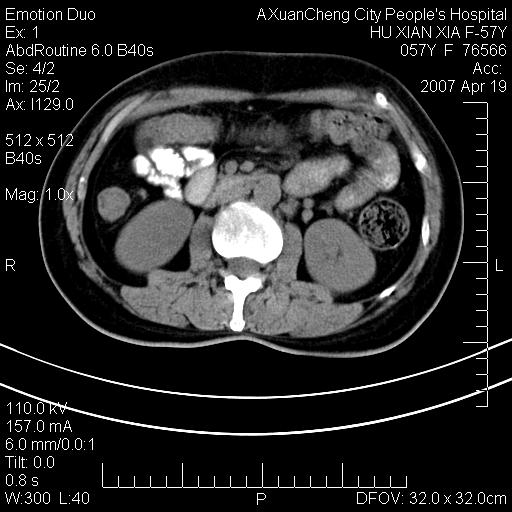

标题: CT7778:[原创]F,57Y腹痛待查,胸片提示肺部占位,应当很典型 [打印本页]

标题: CT7778:[原创]F,57Y腹痛待查,胸片提示肺部占位,应当很典型

胸片提示肺部占位

考虑:1、双侧肾上腺占位.2、肝左叶内侧段不规则低密度灶,建议强化扫描.

忽略了,只以为急腹症,应该支持肺癌肾上腺转移,肺癌患者20-30%发生肾上腺转移

考虑双侧肾上腺占位

双肾上腺占位

双侧肾上腺及腹膜后淋巴结增大,考虑转移,建议查原发灶.

双侧肾上腺占位,建议增强!

降结肠有无问题?双侧肾上腺占位

双侧肾上腺转移瘤?

双侧肾上腺增大,有分叶,密度均匀,考虑转移建议查原发灶

双肾上腺转移瘤

1.双侧肾上腺占位,转移首先考虑。

支持肺癌肾上腺转移,肺癌患者20-30%发生肾上腺转移

双侧肾上腺及腹膜后淋巴结增大,考虑转移,肺转移?

双侧肾上腺结节样肿块,结合肺部肿块,考虑肺癌肾上腺转移。

双侧肾上腺及腹膜后淋巴结增大,结合胸片提示肺部占位,考虑肺癌双侧肾上腺及腹膜后淋巴结转移.